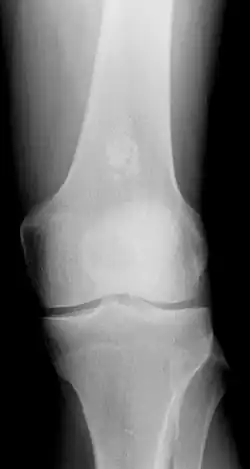

X-ray showing an enchondroma in the femur.

• X-ray – On plain film, an enchondroma may be found in any bone formed from cartilage. They are lytic lesions that usually contain calcified chondroid matrix (a "rings and arcs" pattern of calcification), except in the phalanges. They may be central, eccentric, expansile or nonexpansile.

Differentiating an enchondroma from a bone infarct on plain film may be difficult. Generally, an enchondroma commonly causes endosteal scalloping while an infarct will not. An infarct usually has a well-defined, sclerotic serpentine border, while an enchondroma will not. When differentiating an enchondroma from a chondrosarcoma, the radiographic image may be equivocal; however, periostitis is not usually seen with an uncomplicated enchondroma.